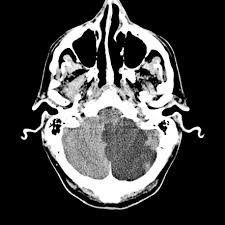

Late Alteplase Thrombolysis for Posterior Circulation Stroke: The EXPECTS Trial